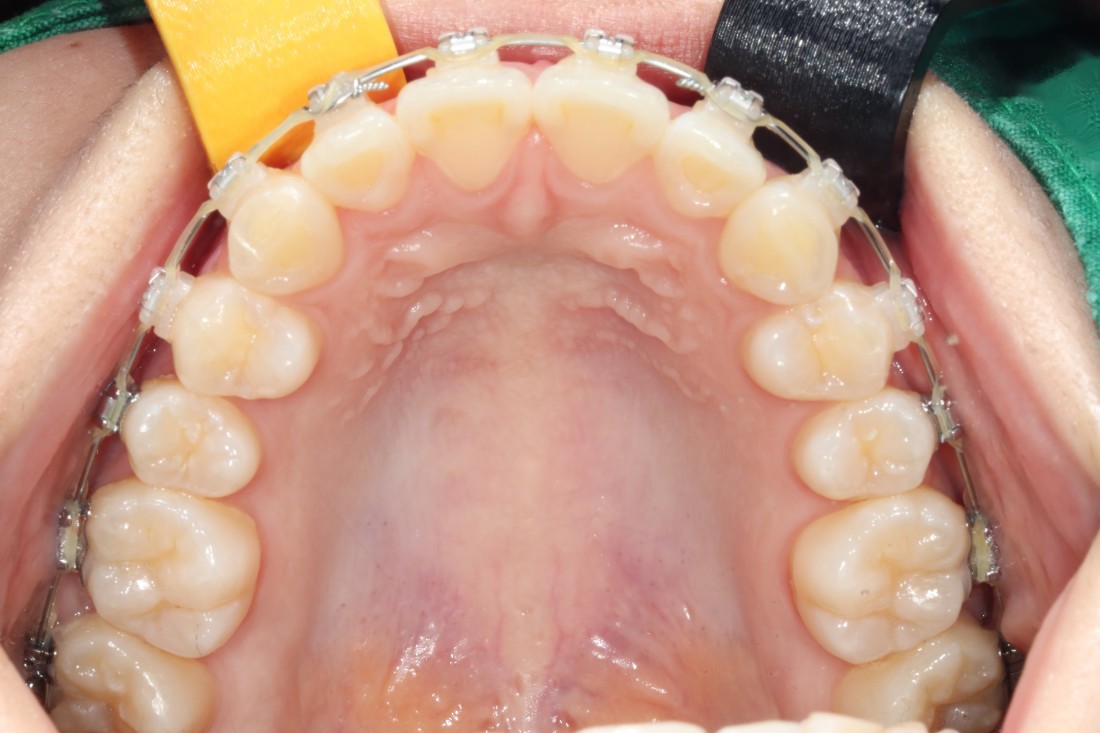

광주 교정치과

충치치료 + 치아교정 동시 케이스

광주 교정치과 추천하는 이유는

전문의 충치치료까지 동시에 가능하여

토탈 구강건강 관리를 받으실 수 있기 때문입니다.

5층은 일반진료센터,

4층은 VIP 치아교정실로 운영되어

치아교정 진료만을 담당하는

교정전담 의료진의 세심한 케어로

광주 교정치과를 추천합니다.